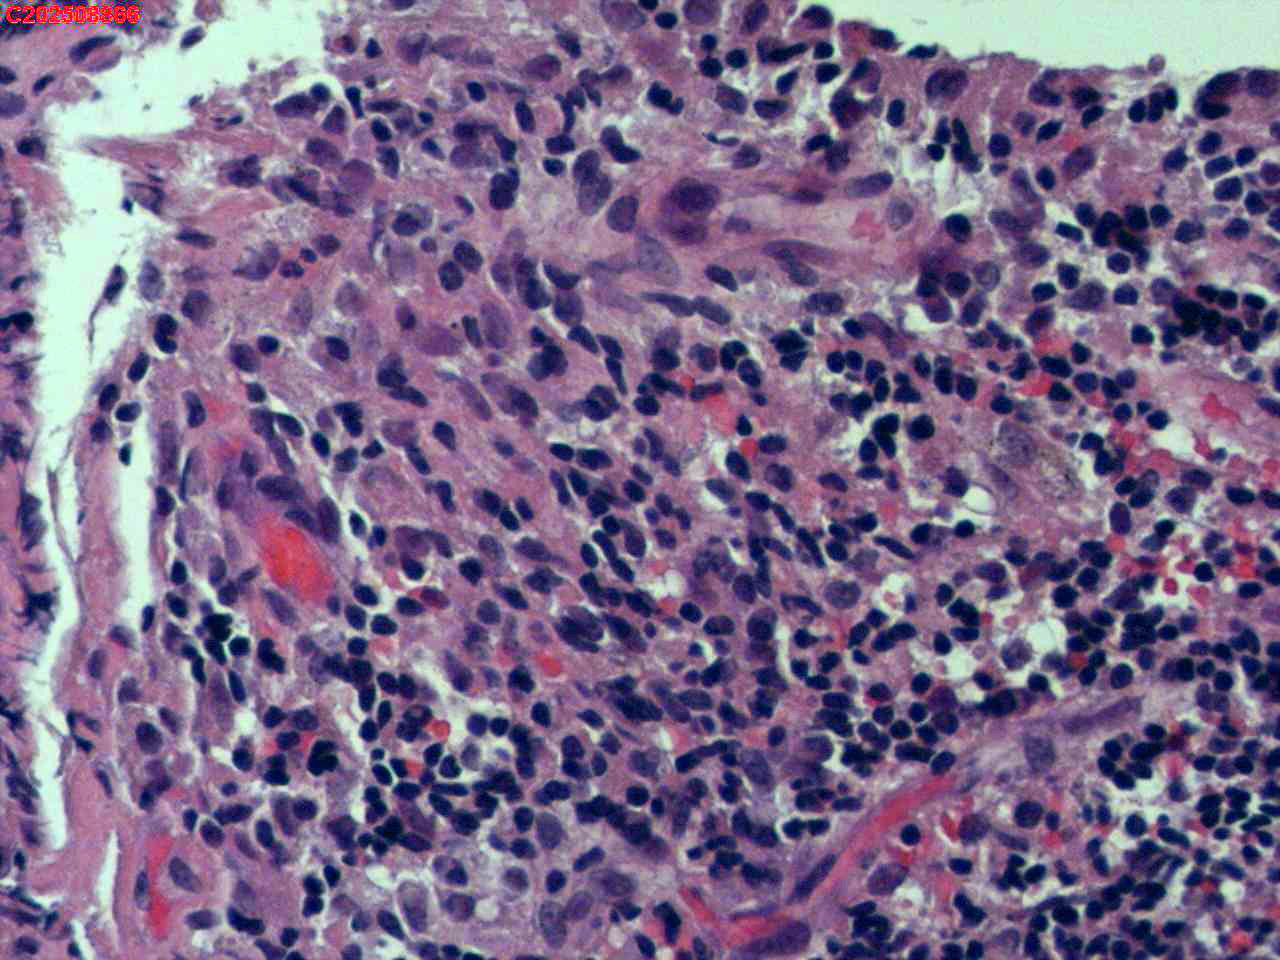

纤支镜咬检

肺TB?Ca?

胸部CT(平扫):考虑双肺感染性病变,结核?支气管炎?请结合临床及其它检查。

标本名称

右肺上叶后段开口咬检组织

大体所见

右肺上叶后段开口处粘膜不规则增生。

肉芽肿性炎的可能性大些!

有坏死,深染变形的细胞需要排一排神经内分泌肿瘤。